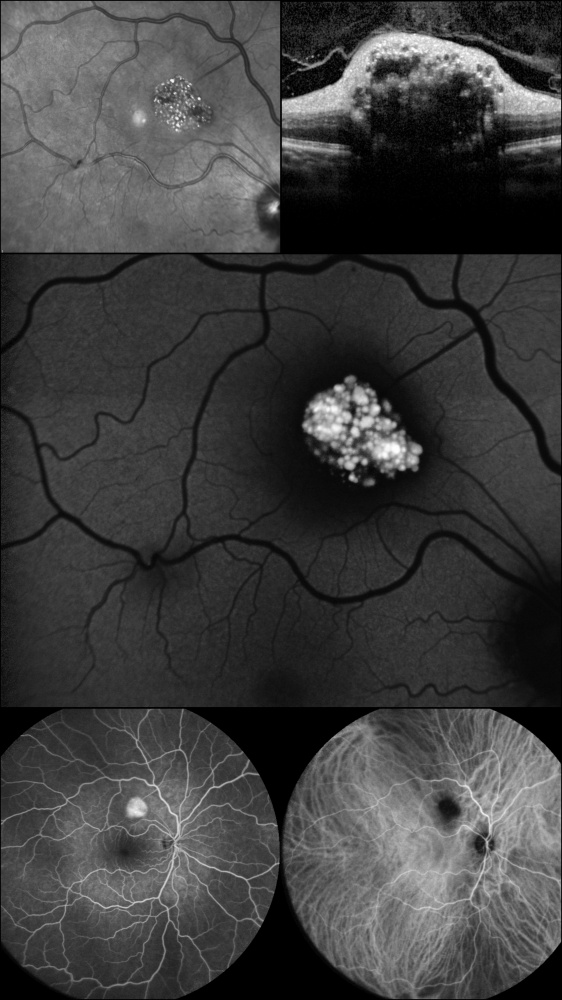

Título: Shine bright like a Diamond: Retinal Astrocytic Hamartoma

Autor: PEDRO MOTA MOREIRA

Coautores: Pedro Marques Couto, Ana Gama e Castro, Teresa Bragança

Instituição: Unidade Local de Saúde de São João

Descrição: Astrocytoma; Hamartoma; Retinal Astrocytic Hamartoma; Tuberous Sclerosis Complex; Multimodal Imaging